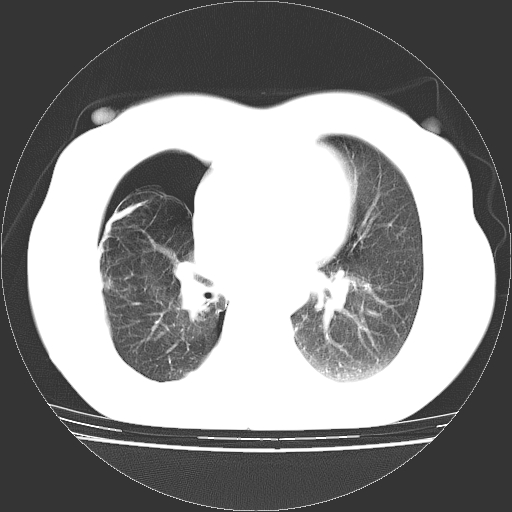

以下是引用zhangzhongshou在2008-3-22 12:52:00的发言:[br]1、右侧液气胸。[br]2、腹水。建议进一步检查。

以下是引用鲁巨ct在2008-3-22 14:10:00的发言:[br]1、右侧液气胸,右中下叶节段性不张。[br]2、腹水,建议上腹部ct检查

以下是引用zjzjr在2008-3-22 17:19:00的发言:[br]1、右侧液气胸,右下叶节段性不张。[br]2、腹水,建议上腹部ct检查